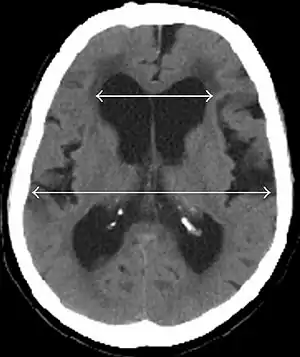

Evan's index is the ratio of maximum width of the frontal horns to the maximum width of the inner table of the cranium. An Evan's index more than 0.31 indicates hydrocephalus.[2] | |